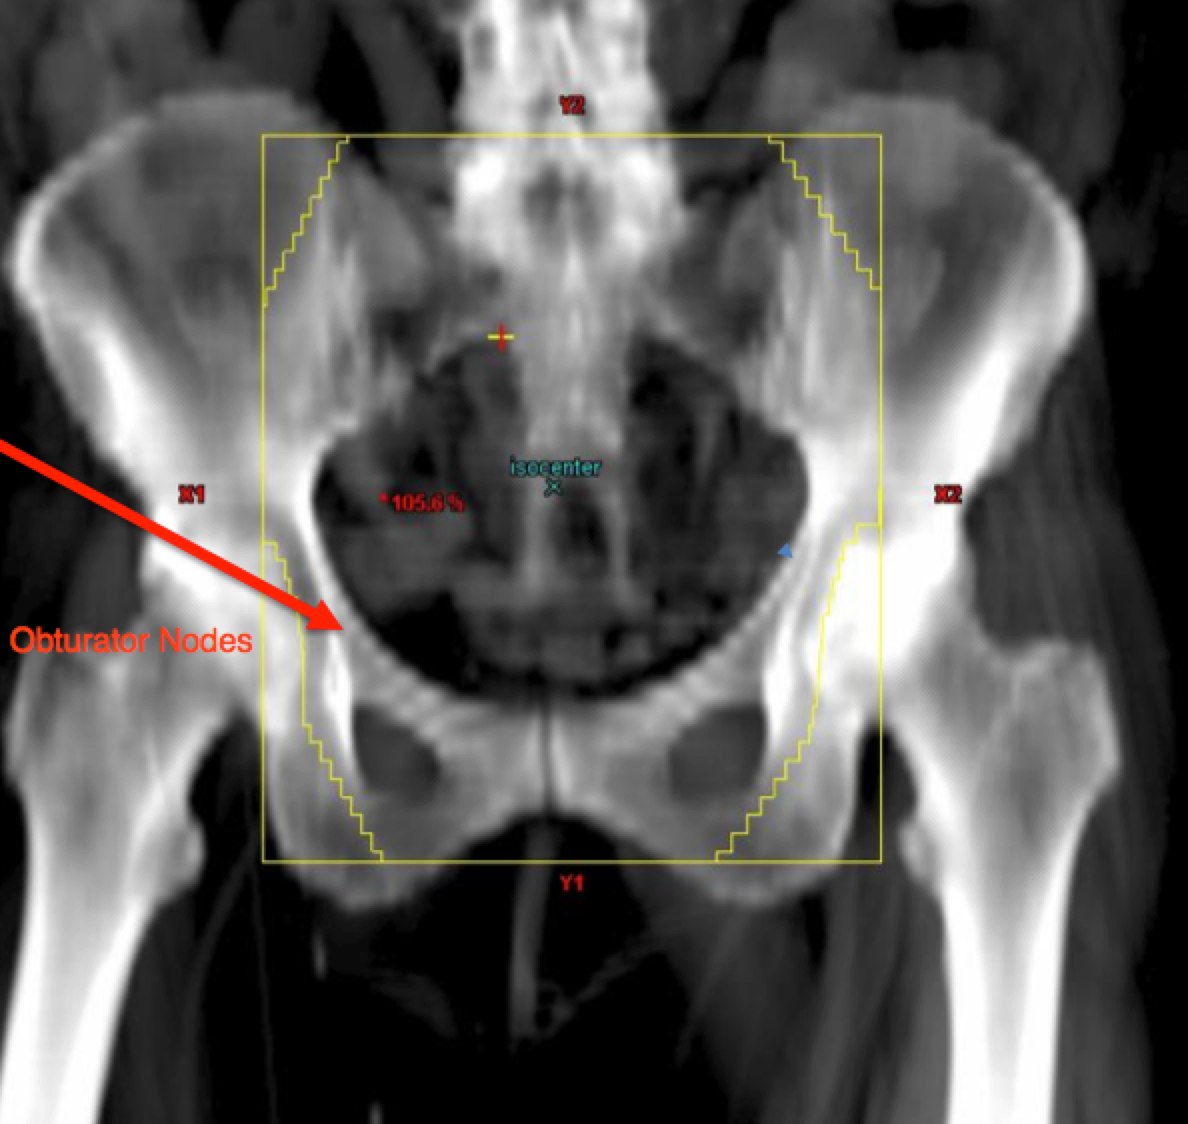

To identify the obturator nodes the following landmarks may be used. (Note: this works for any pelvis where one wishes to find the obturator nodes):